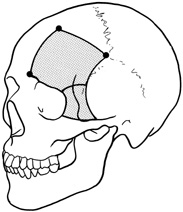

Fig. 16. A. Patient with right orbital cellulitis. B. Coronal CT scan demonstrating subperiosteal abscess formation from frontal and ethmoidal sinusitis. C. Frontoethmoidal orbitotomy incision marked for abscess drainage.

A frontoethmoidal, or Lynch, skin incision is marked halfway between the medial canthus and bridge of the nose. It extends superiorly and inferiorly in a curved fashion approximately 2 to 3 cm (Fig. 16). The exact limits of the incision depend on the location of the underlying lesion. Injection of local anesthetic with epinephrine provides vasoconstriction, which greatly enhances hemostasis. After the skin is incised, a unipolar cutting cautery is used to extend the incision deeply to the periosteum. Bleeding may be encountered, especially in the area of the angular artery and vein. Exposure is enhanced with 4-0 silk sutures passed into the orbicularis muscle and clamped to the drapes.

The periosteum is exposed and incised with a Freer elevator and then is reflected off the bone posteriorly. It is generally quite adherent to the curved contour of the medial canthal bones, especially at the medial canthal tendon. The anterior lacrimal crest is encountered inferiorly. Care should be taken not to damage the lacrimal sac with the elevator. The posterior lacrimal crest is visible behind the sac. Adequate mobilization of the periosteal connections to the anterior lacrimal crest gives a large area of exposure. The periosteal elevation is carried superiorly in the area of the trochlea. Elevation of the periosteum opens the subperiosteal space. Blood or pus caused by fracture or infection, if present in this space, is encountered at this point.